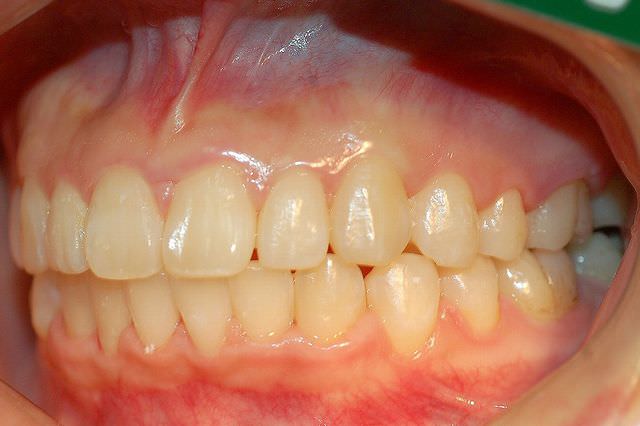

治療前

叢生 治療前

治療後

叢生 治療後

主訴 歯並びが気になる

診断名あるいは主な症状 叢生 乱ぐい歯

年齢 13歳0ヶ月

治療に用いた主な装置 ブラケット装置 スタンダードエッジワイズ法

抜歯部位 非抜歯

治療期間 2年5ヶ月

治療費概算 70万+月々の調整料

リスク副作用 歯の根が吸収して短くなる場合があります。

歯茎が痩せて下がる場合があります。

舌で歯を押す唇を噛む等の癖が改善されない場合は、治療期間が長引く場合があります。

定期的に通院できない、キャンセルが多い場合は治療期間が長引きます。